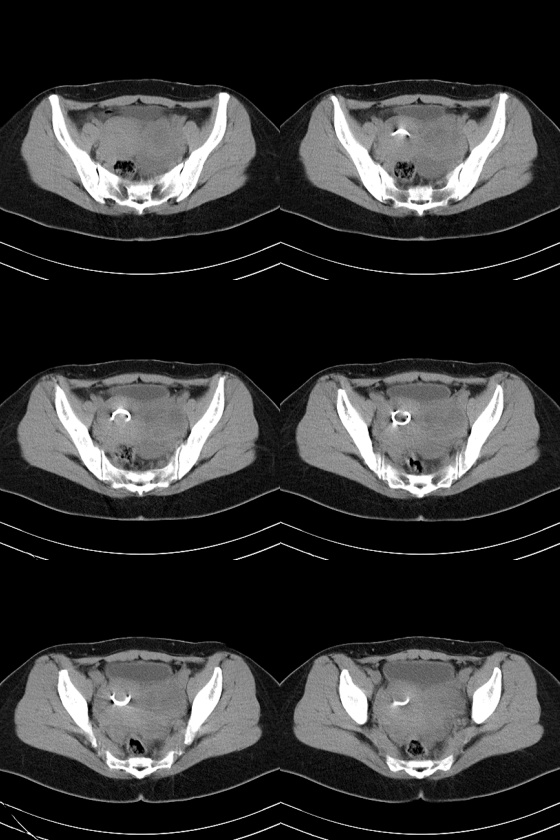

47岁女性,下腹部疼痛伴发热(38度)半月。b超提示宫底见3.0cm弱回声团块,边界清楚,形态规则,左侧附件区见不规则形态杂乱回声团块,其内可见液性暗区。b超同时提示肝脏见多个1.5cm的占位性病变。患者不同意做增强扫描。

没看见肝呀。不增强,只能猜。

1、考虑左侧卵巢癌并肝转移(依据:左侧附件区囊实性包块,盆腔有积液,肝脏有多个占位),当然没有增强只是提示一种可能性。

2、病人有发烧,又不能排除左侧输卵管感染性病变,如病人不增强那就抗炎治疗后复查有助诊断。